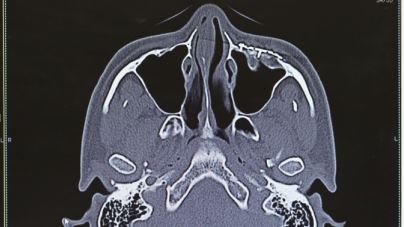

形成外科の治療対象は多岐にわたりますが、主な対象として、腫瘍、外傷、先天異常、美容外科が挙げられます。当院では美容外科、乳房再建以外のほぼすべての領域をカバーしています。腫瘍は皮膚・皮下の良性腫瘍、皮膚癌、外傷は顔面外傷、顔面骨骨折、熱傷、傷痕などの患者さんをご紹介いただいており、積極的に治療を行っています。特に顔面は整容的・機能的に重要な部分が集中しており、顔面を専門として扱う外科でもあります。生まれつきの病気は、目の変形(先天性眼瞼下垂、睫毛内反など)、耳の変形(副耳、耳前瘻孔など)、手足の変形(多指症、合指症など)などの小児形成外科分野の手術も積極的に行っており、機能的・整容的改善のみならず、患児の精神的な発育にも良い影響を与えます。眼瞼下垂は身近な疾患ですが、「瞼が下がってきた、ものが見えにくい、目が疲れる」などの症状が生活の質の低下を招きます。このような症状に対して手術により改善し、社会参加の機会を増やすことにも繋がります。また、治療対象は全身のあらゆる部位に及ぶため、形成外科単独で治療にあたるだけでなく、他の多くの診療科との連携においても、存在意義を発揮する分野であります。